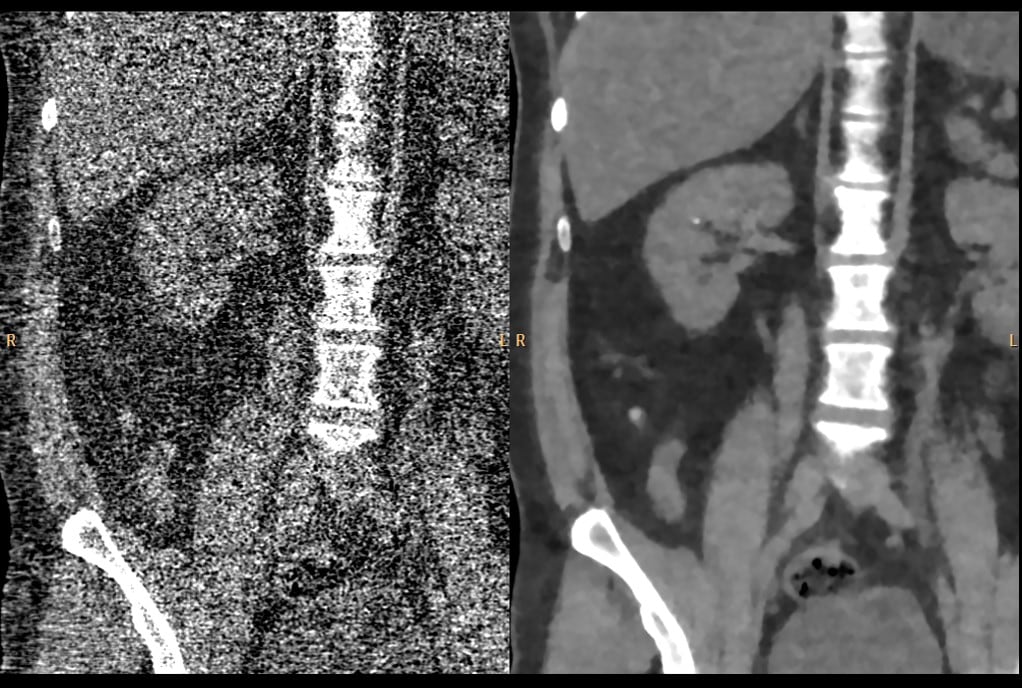

Chungang University Hospital “PCTA (prospective coronary CTA) showed significantly improved subjective and objective image quality parameters for coronary vessels with IMR compared to FBP and iDose⁴. PCTA using 80KVp and IMR could be applicable in routine clinical setting with less radiation dose.”

South Korea

Dr. Jae Suung Seo, Dr. Sung Bin Park & Team